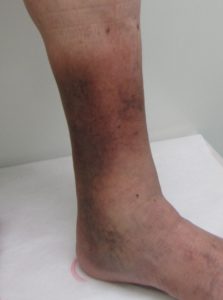

足の湿疹(しっしん)、皮膚硬化

下肢静脈瘤は進行すると皮膚炎を起こすことがあります。

コブができている周囲の皮膚や、足首の周辺に出るのが特徴です。

かゆみが強く、薬をつけてもいったんは良くなりますが完治しません。

皮膚にくり返し炎症を起こすと、段々と固く黒くなっていきます。

これを脂肪皮膚硬化症(しぼうひふこうかしょう)と言います。

色素沈着

いったん色素沈着が起こると、下肢静脈瘤を治療してもなかなかよくならないで、色素沈着が起こる前に治療を行うのが賢明です。